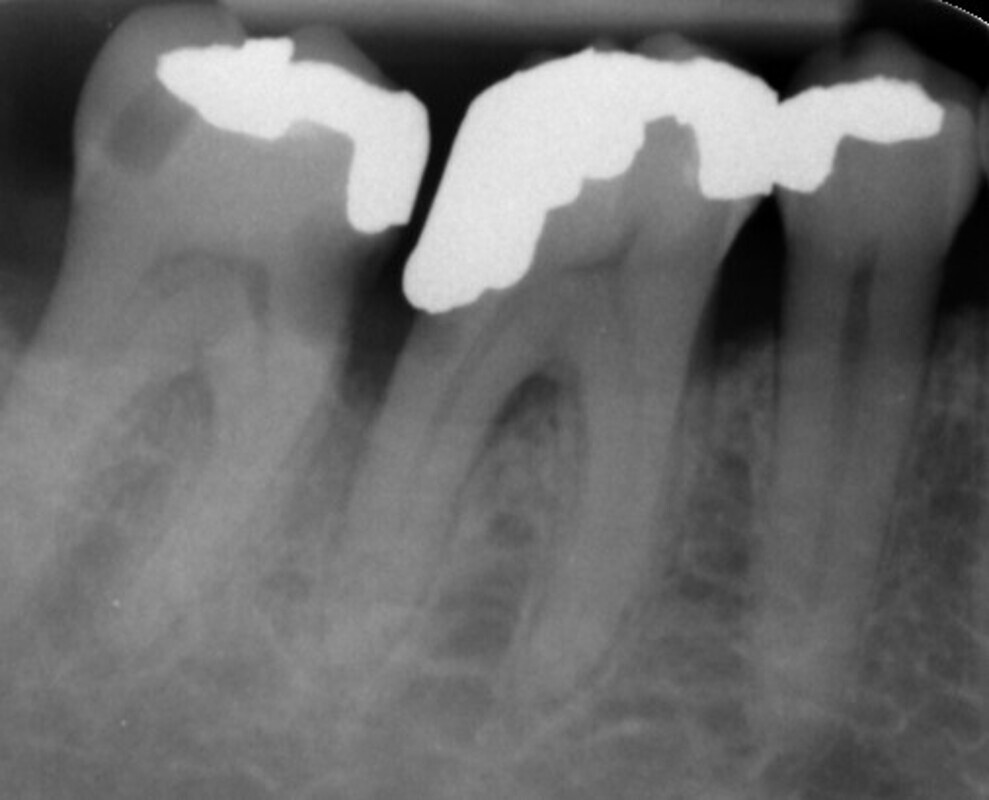

Fig. 2: Pre-op radiograph.

A 57-year-old male patient presented by referral with two failing molars, teeth #46 and 47. The patient had a clear medical history, and both molars exhibited extensive caries and restoration (Figs. 1–6).